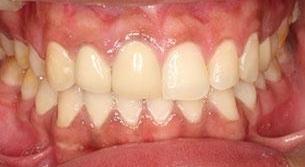

This adult patient did not like the their outdated, discoloued crowns on their upper front teeth. A laser gum surgery made a symmetrical gum line on the two upper front central teeth, and then we placed three new crowns to give a much more natural looking smile!